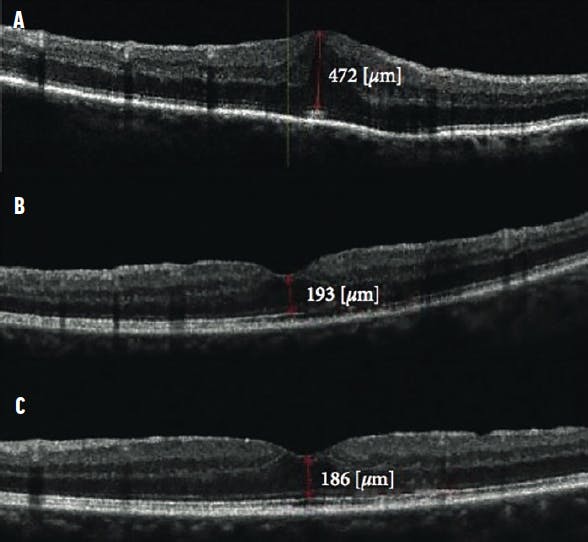

Intraoperative complications, especially peripheral retinal tears and the need for laser photocoagulation, were noted. The duration of surgery was recorded in five categories: 30 to 45 minutes, 46 to 60 minutes, 61 to 90 minutes, 91 to 120 minutes, and more than 120 minutes. Data gathered during follow-up visits at 1 week, 6 months, and final follow-up included BCVA, central macular thickness (CMT), and complications (Figures 1 and 2).

Figure 1. These OCT scans show a patient who underwent limited vitrectomy with ERM removal. The preoperative scan (A) shows the ERM with CMT of 472 µm with BCVA measuring 0.5 logMAR. The 1-month postoperative scan (B) shows CMT reduced to 193 µm with BCVA improvement to 0.8. The 1-year follow-up scan (C) shows CMT of 186 µm with normal foveal contour and vision improvement to 0.9 logMAR.